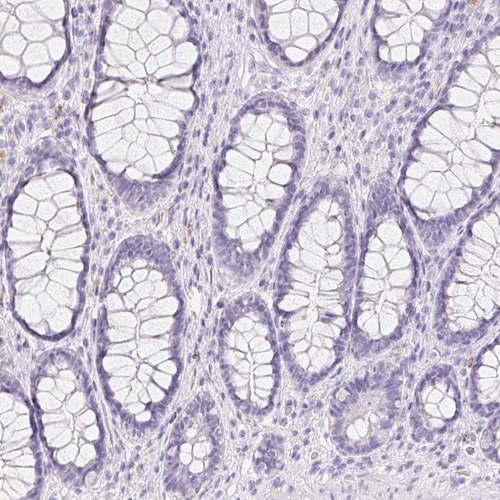

Immunohistochemical staining of human skin shows strong membranous and cytoplasmic positivity in sweat duct cells and secretory cells.